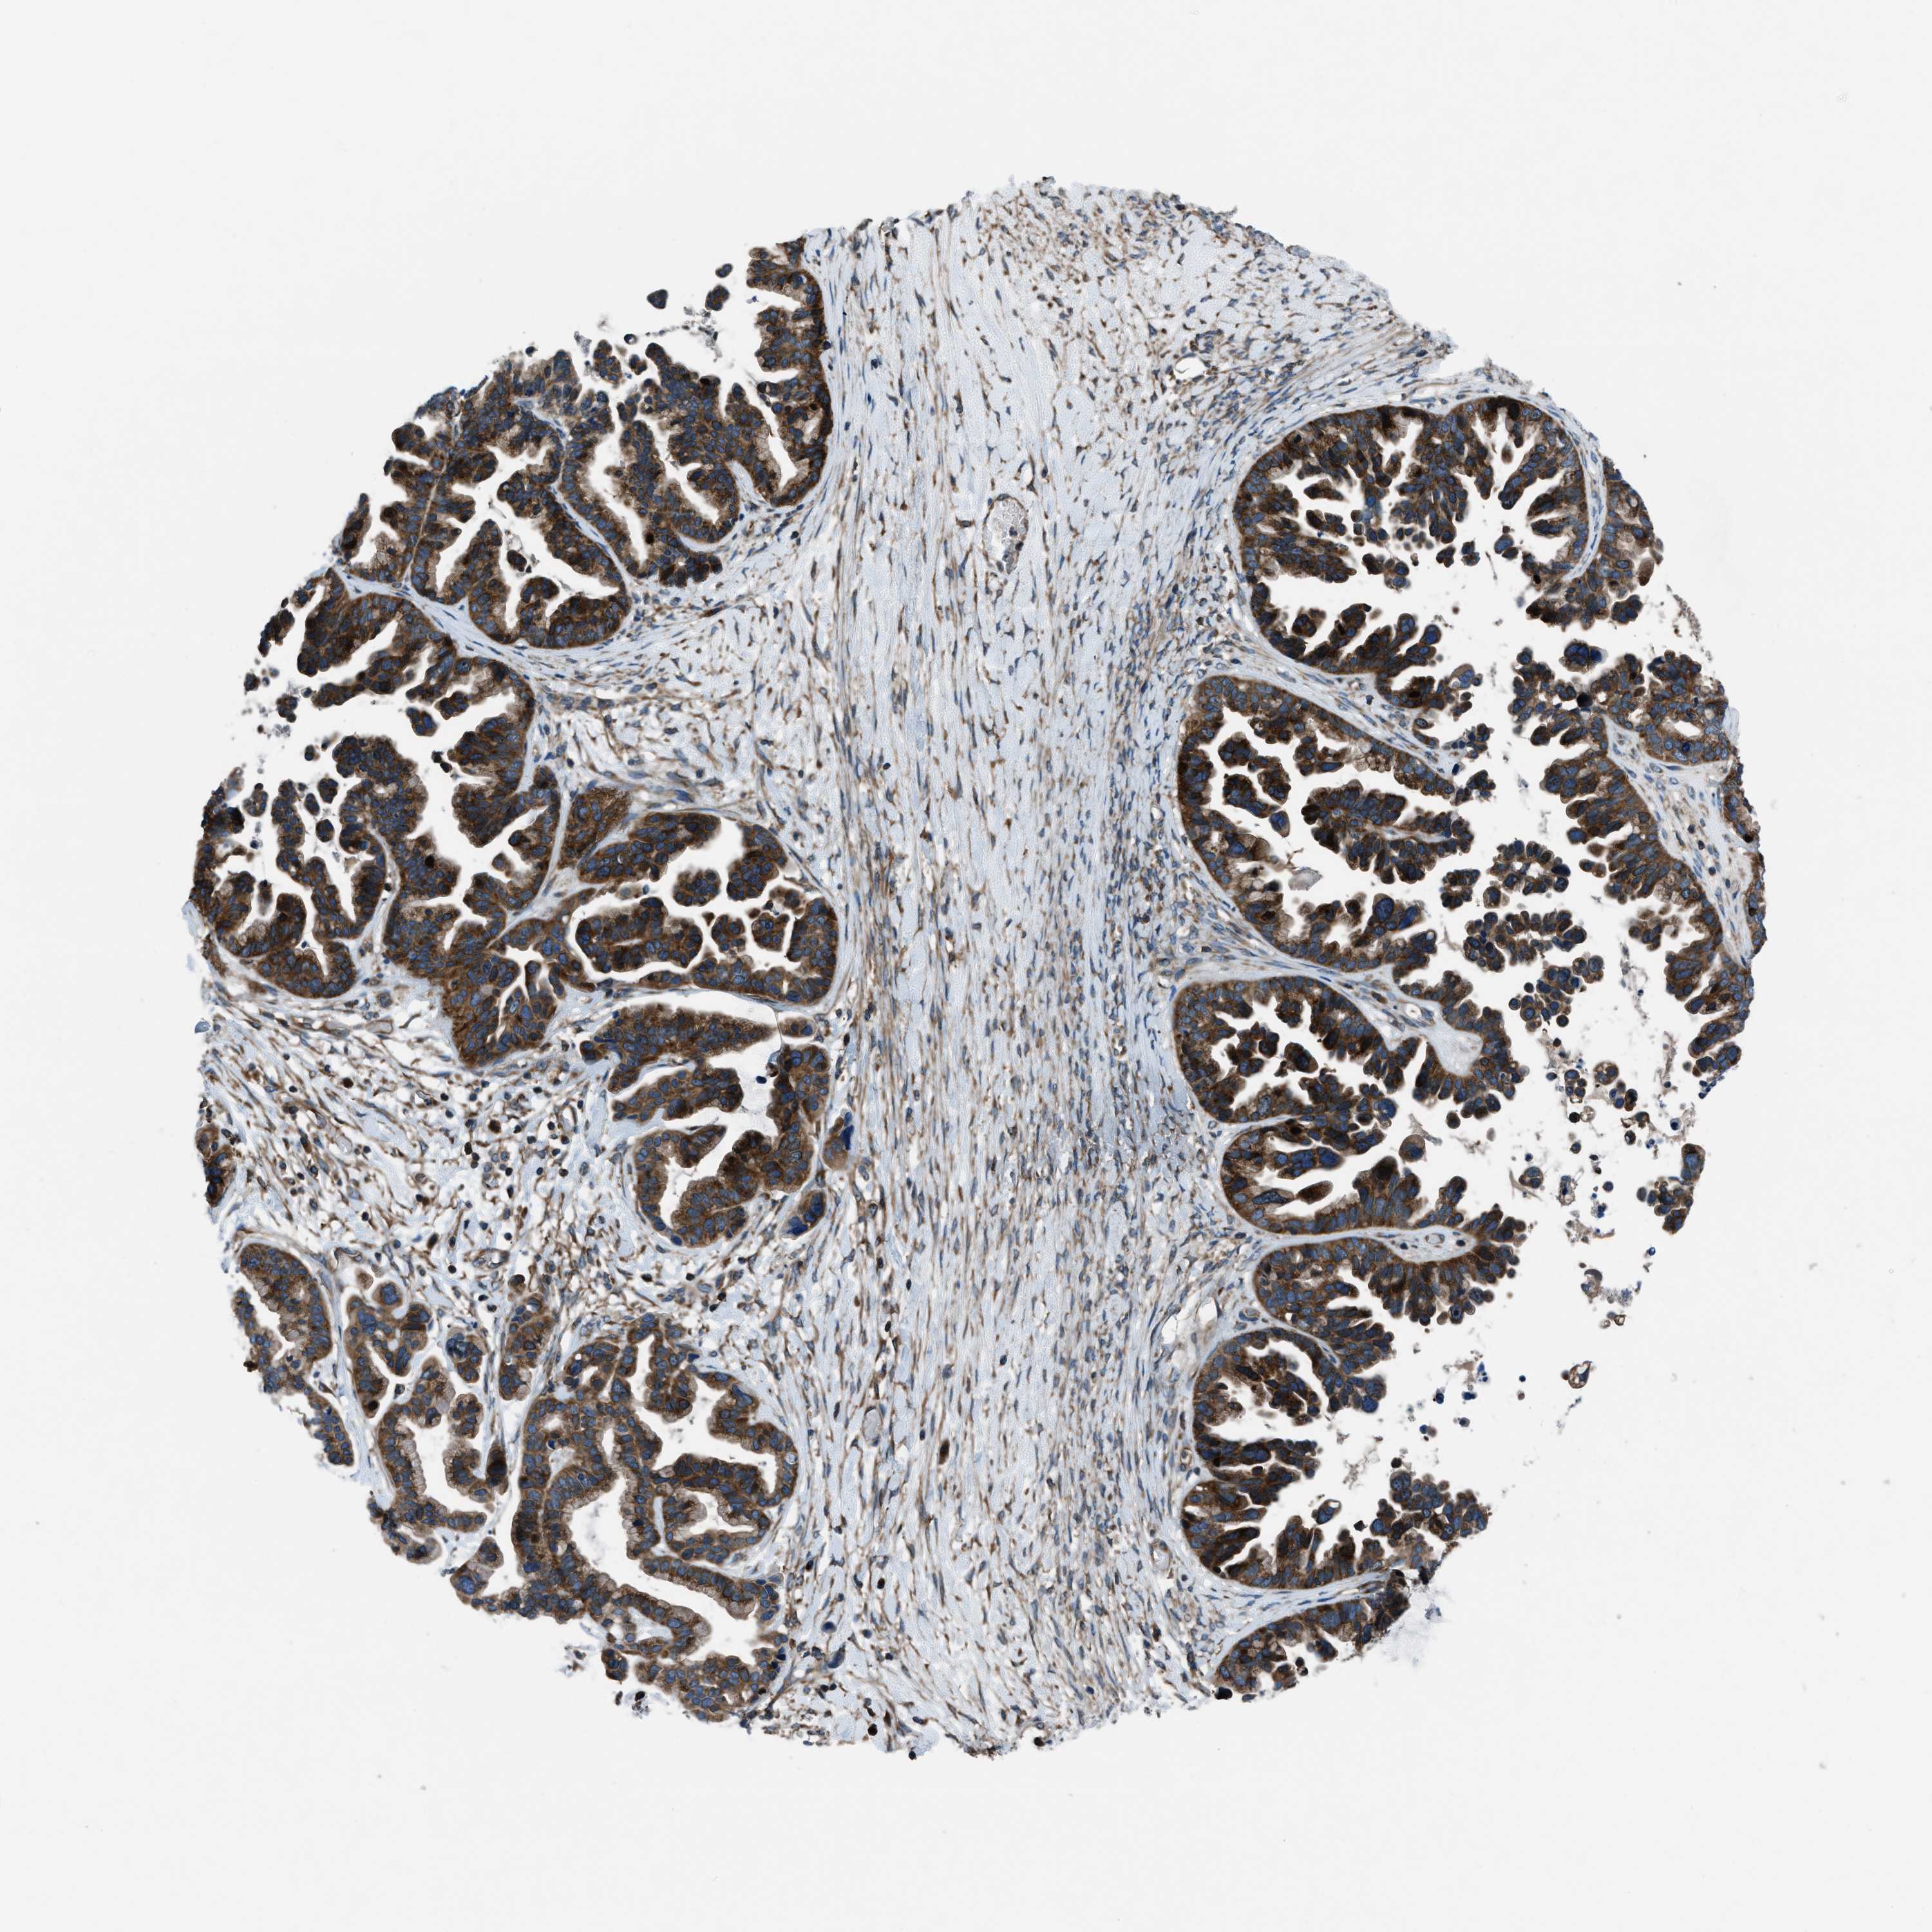

OVARIAN CANCER - Protein expressioni

A mouse-over function shows sample information and annotation data. Click on an image to view it in a full screen mode. Samples can be filtered based on level of antibody staining by selecting one or several of the following categories: high, medium, low and not detected. The assay and annotation is described here.

Note that samples used for immunohistochemistry by the Human Protein Atlas do not correspond to samples in the TCGA dataset.

Antibody stainingi

Antibody staining in the annotated cell types in the current human tissue is reported as not detected, low, medium, or high, based on conventional immunohistochemistry profiling in selected tissues. This score is based on the combination of the staining intensity and fraction of stained cells.

Each image is clickable and will lead to virtual microscopy that enables deeper exploration of all samples and also displays staining intensity scores, fraction scores and subcellular localization as well as patient and tissue information for each sample.

Antibody HPA016649

Antibody HPA018152

Cystadenocarcinoma, serous, NOS

Carcinoma, endometroid

Cystadenocarcinoma, mucinous, NOS

Carcinoma, NOS